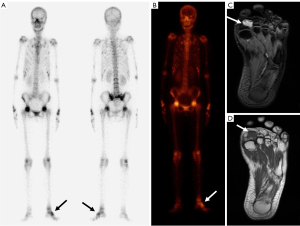

PET/CT (18F-FDG/68Ga-DOTATATE) showed that the left palmar tubercle was associated with increased glucose metabolism and increased expression of the somatostatin receptor. It also indicated osteomalacia in multiple bilateral ribs and the pelvis with L5 double vertebral arch isthmus fractures (Figure 3).

MRI of the left foot showed a volar nodule of the first metatarsophalangeal joint, demonstrating an intermediate T1 signal with T2 hyperintensity (Figure 3). Ultrasound examination showed a heterogeneous hypoechoic oval mass 27 mm ×16 mm ×13 mm in size between the first and second metatarsophalangeal joints of the palm of the left foot with a clear boundary and a regular shape (Figure 4A). The mass was adjacent to the first and second metatarsal bones and the flexor digitorum tendon. A rich blood flow signal was detected in the mass (Figure 4B). These results, in combination with the patient’s clinical history and blood biochemistry, suggested the presence of PMT.

Imaging examinations have important clinical value in the diagnosis and postoperative follow-up of PMT. Tumors should be identified through a stepwise approach, including functional imaging, and the identification should be confirmed with anatomic imaging, such as CT, MRI, or ultrasound (20). The imaging features of PMT are as follows: A unique feature best demonstrated on CT is the presence of the internal matrix, which is likely correlated with matrix calcification. In an MRI examination, the majority of lesions demonstrate an intermediate T1 signal with T2 hyperintensity. The characteristic feature of a PMT on PET/CT is metabolically active neoplasms (8,21,22). Ultrasound examination can determine the size, boundary, echo, and blood flow signal of PMT lesions. The ultrasound findings of PMT are a solid hypoechoic tumor structure with a heterogeneous internal echo. The heterogeneous hyperechoic echo corresponds to the unique calcium deposition in the pathology of the PMT, while the anechoic structure corresponds to the cyst in the pathology of the PMT. Color Doppler flow imaging shows abundant blood flow, which corresponds to many abnormal blood vessels of PMT in the pathological examination. CT has advantages for bone imaging, but it uses radiation, which cannot be used repeatedly during the follow-up of patients. MRI has the highest soft tissue resolution, but is less economically viable for price for patients. Ultrasound examination provides images in real-time, requires no radiation, and is inexpensive. However, it is weak in detecting deep positions, meaning some lesions cannot be detected and identified clearly. Therefore, the multiple image modality should be applied to diagnose and identify PMTs.

In this study, we described 2 cases that had clinical, biochemical, and imaging evidence of PMT. When the doctor found a mass on the surface of 2 patients, an imaging examination was performed for each patient. Therefore, this kind of solid tumor can be identified as a PMT based on the hypoechoic imaging manifestations, rich blood supply, and intermediate T1 signal with T2 hyperintensity, combined with the patient’s symptoms, low phosphate level, and high FGF23 level. A combination of laboratory tests and imaging examinations could provide a precise diagnosis of PMT. The image characteristics of PMT are extremely helpful in diagnosing and localizing a PMT. These characteristics include the heterogeneous hypoechoic solid structure, rich blood flow, the presence of an anechoic cyst and hyperechoic calcification on ultrasonography, the presence of an internal matrix in CT, and the intermediate T1 signal with T2 hyperintensity in MRI.